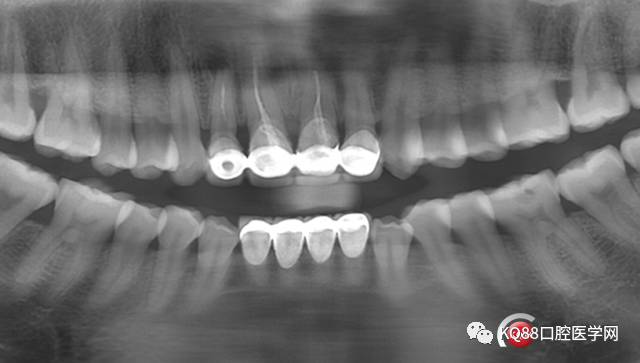

可见A2根尖偏远中有暗影,12 11 21根管治疗均不完善,然后开始拆冠,牙周治疗,根管治疗

还是根尖偏远中的地方有一点,但是明显感觉比第一次全景时范围小了,好了开始准备根尖手术,